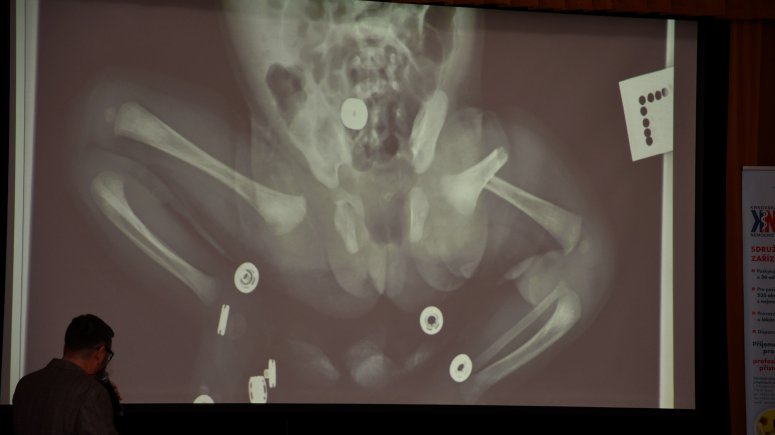

Následoval blok lékařů krnovské ortopedie, kteří odprezentovali výhody nové počítačové navigace při výměně velkých kloubů a nejmodernější postupy při operacích kostí i tkání. V řadě zajímavých příkladů z praxe představili také příběh měsíčního dítěte léčeného se zlomeninou stehenní kosti. „Hlavní zajímavostí je neuvěřitelná rychlost hojení a adaptabilita dětského organismu. Do 5 let věku se tyto zlomeniny obvykle řeší bez operačního zákroku, úvazem dítěte do závěsu, který umožňuje přirozenou obnovu poškozené kosti. V tomto případě k plné nápravě zdraví došlo za pouhých 48 dní,“ vysvětlil primář ortopedického oddělení MUDr. Mojmír Svoboda.

Foto 1, 2, 3, 4, 5, 6 – Krnovská nemocnice uspořádala pátý ročník Dne akutní medicíny MUDr. Vladimíra Šiguta st. Poslechnout si zajímavé přednášky přišly dvě stovky zdravotníků z celého regionu.                                                                               Foto: Jiří Krušina